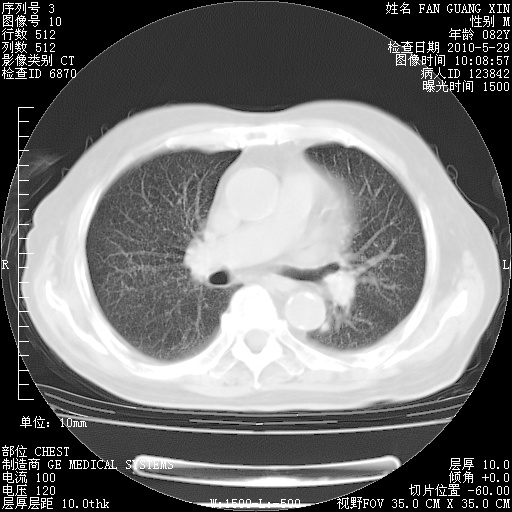

再治疗10天后的肺部CT